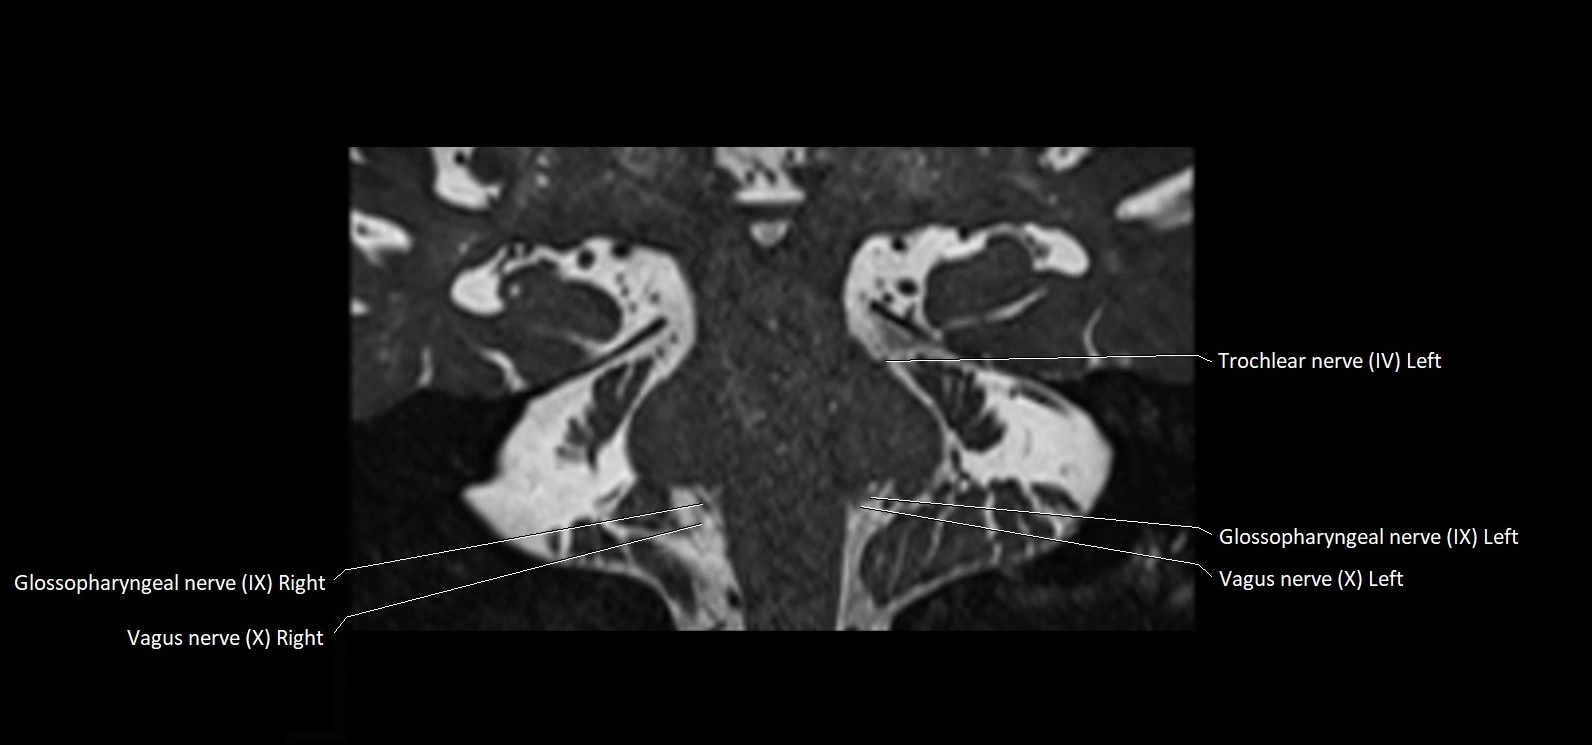

MRI Appearance

• The abducens nerve is a small, thin, linear structure

• Best visualized on high-resolution T2-weighted 3D MRI sequences (e.g., FIESTA or CISS)

• Seen as a hypointense (dark) line running from the brainstem at the pontomedullary junction, traversing the prepontine cistern, and entering Dorello’s canal under the petrosphenoidal ligament, then into the cavernous sinus, and finally the orbit

• May be challenging to visualize in standard MRI due to its small size

• Pathology may be inferred by absence, displacement, or enhancement of the nerve

MRI images

image